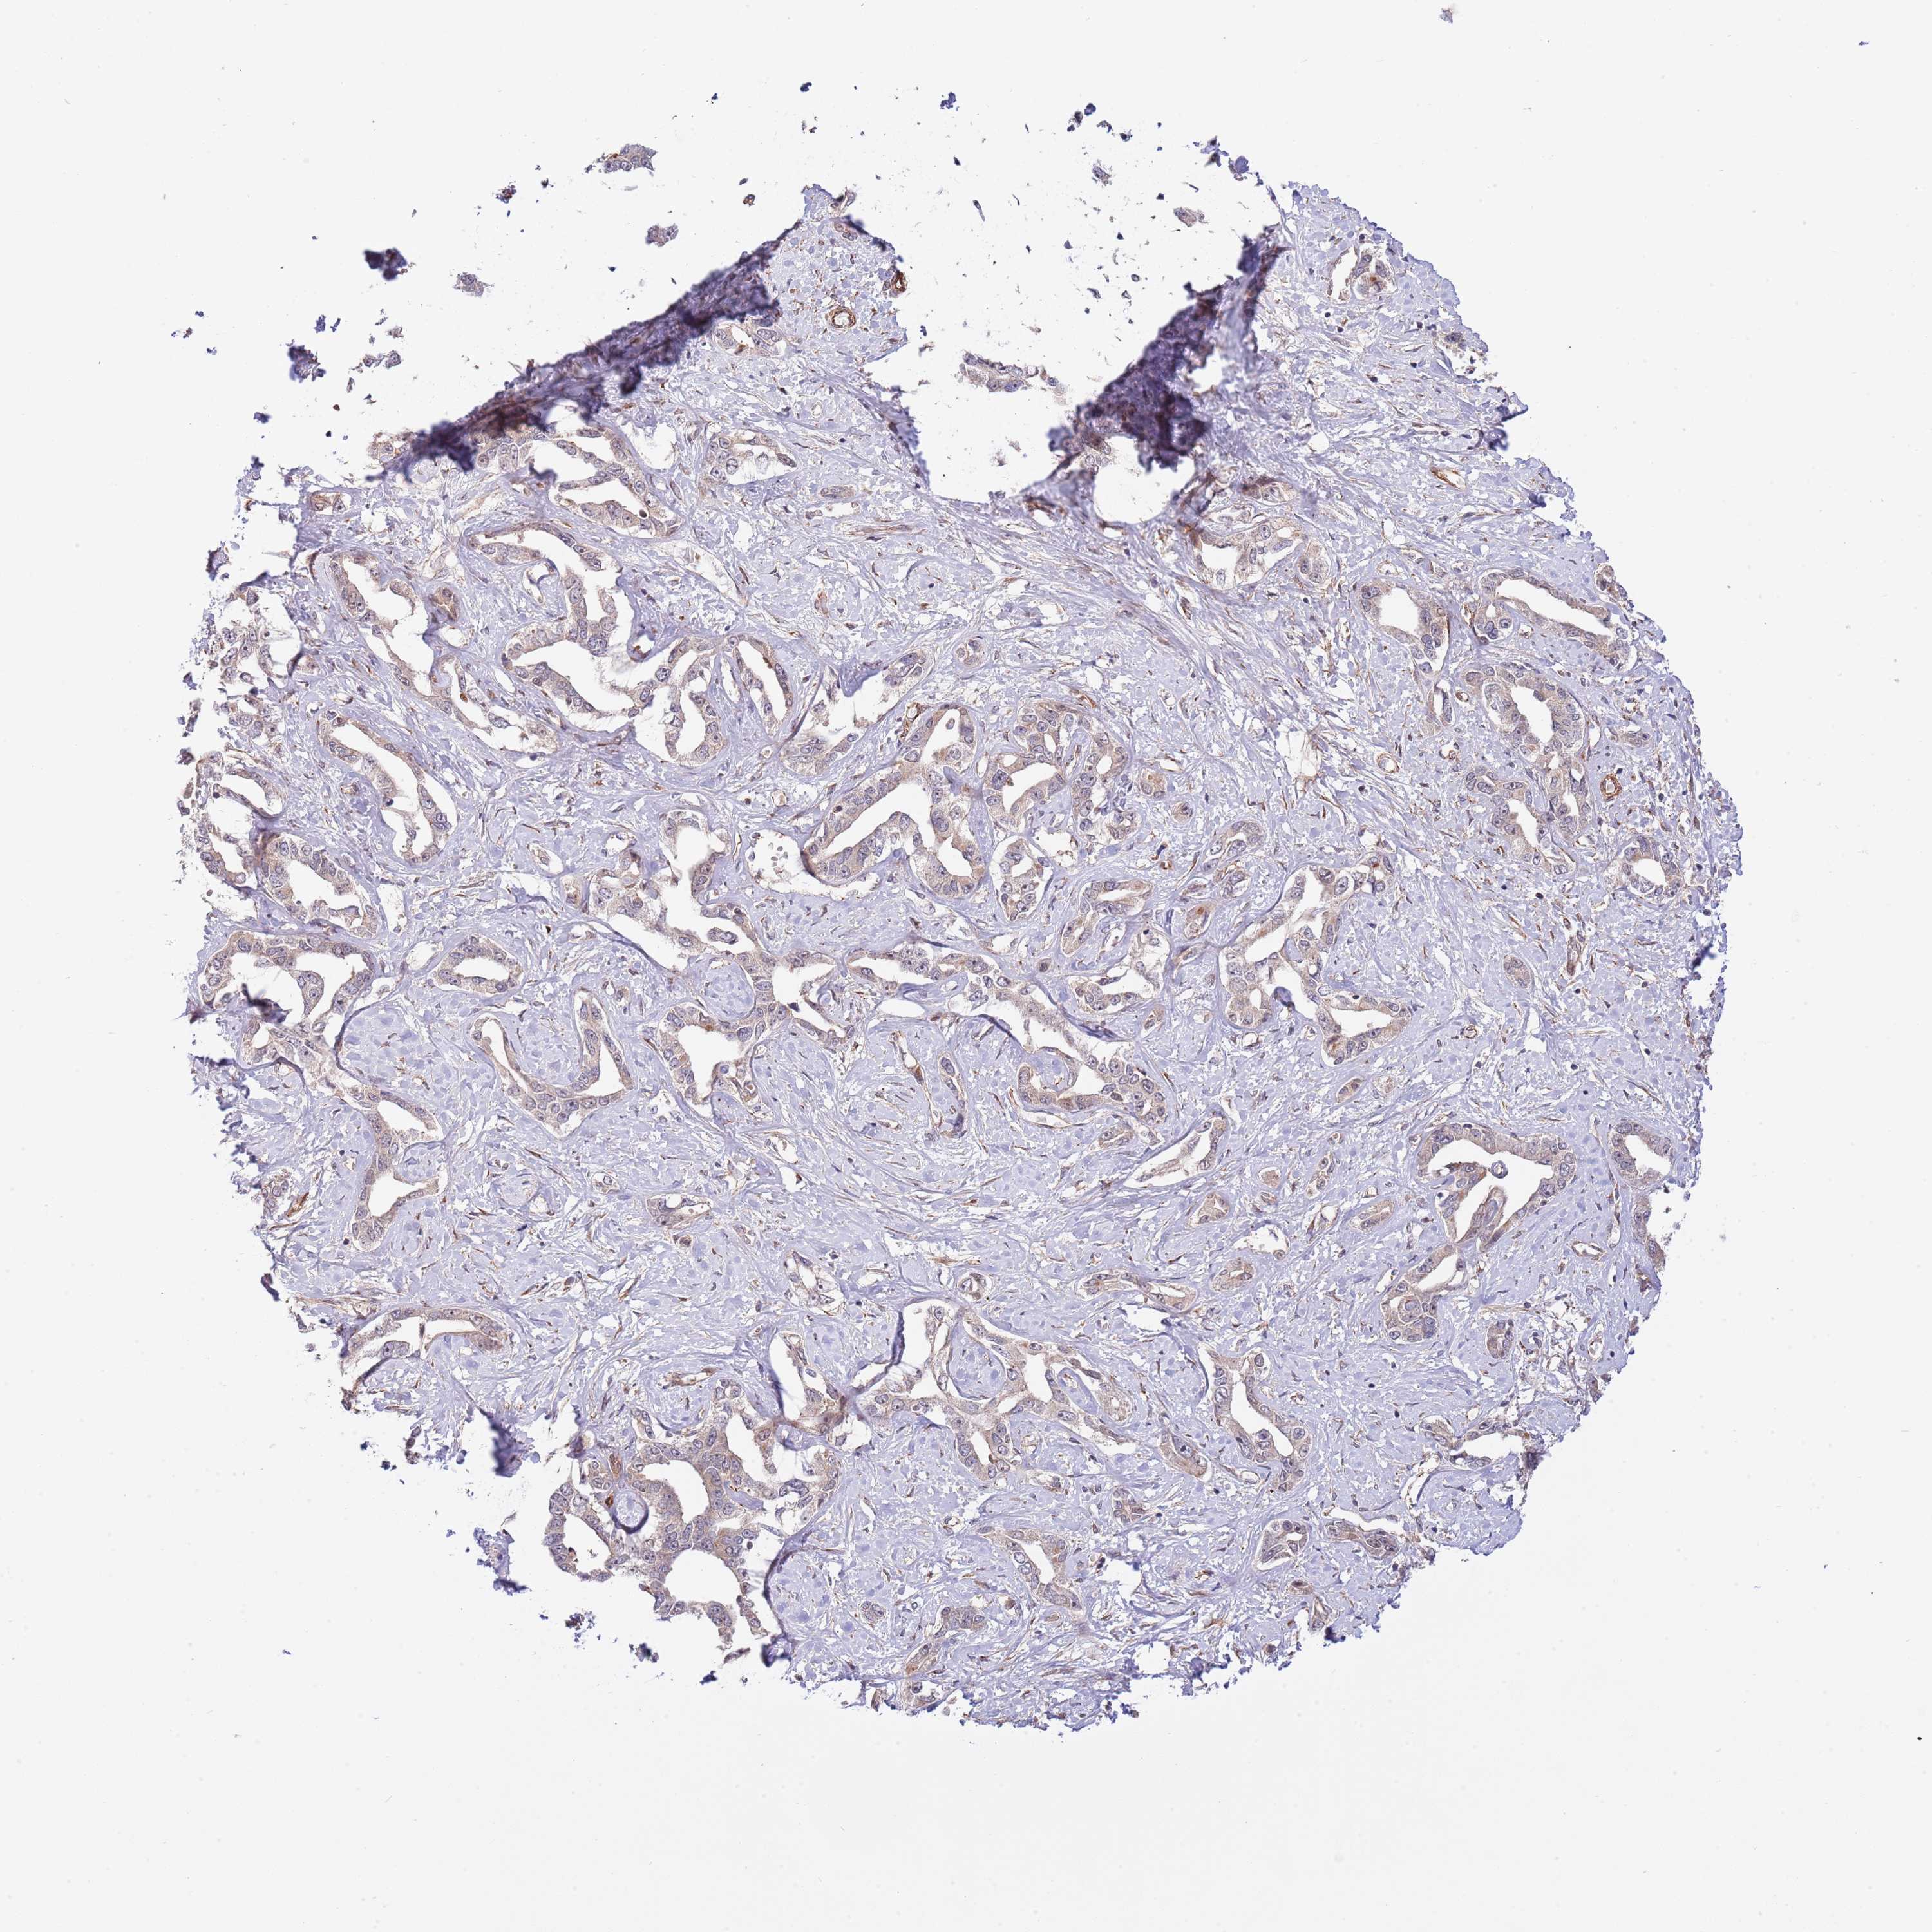

LIVER CANCER - Protein expressioni

A mouse-over function shows sample information and annotation data. Click on an image to view it in a full screen mode. Samples can be filtered based on level of antibody staining by selecting one or several of the following categories: high, medium, low and not detected. The assay and annotation is described here.

Note that samples used for immunohistochemistry by the Human Protein Atlas do not correspond to samples in the TCGA dataset.

Antibody stainingi

Antibody staining in the annotated cell types in the current human tissue is reported as not detected, low, medium, or high, based on conventional immunohistochemistry profiling in selected tissues. This score is based on the combination of the staining intensity and fraction of stained cells.

Each image is clickable and will lead to virtual microscopy that enables deeper exploration of all samples and also displays staining intensity scores, fraction scores and subcellular localization as well as patient and tissue information for each sample.

Antibody HPA019062

Antibody HPA043230

Staining

High

Medium

Low

Not detected

Intensity

Strong

Moderate

Weak

Negative

Quantity

>75%

75%-25%

<25%

None

Location

Nuclear

Cytoplasmic/membranous

Cytoplasmic/membranous,nuclear

Cholangiocarcinoma

Carcinoma, Hepatocellular, NOS